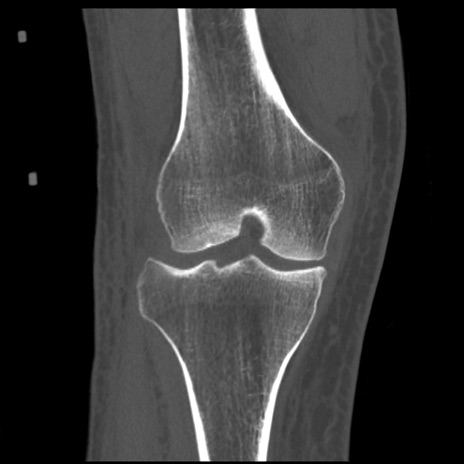

症例28 右膝関節CT(冠状断像)

右膝関節CT